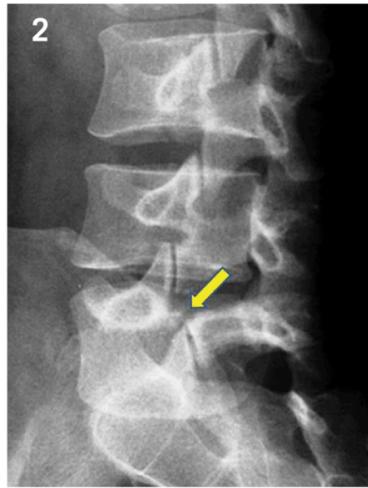

Radiographic “Scottie Dog” Sign

Posterior oblique views show:

- Normal: Scottie dog profile in yellow

- Spondylolysis: Scottie dog appears to be wearing a collar

- Spondylolisthesis: Scottie dog appears decapitated

Diagnostic Imaging

- Oblique view: Shows decapitated Scottie dog